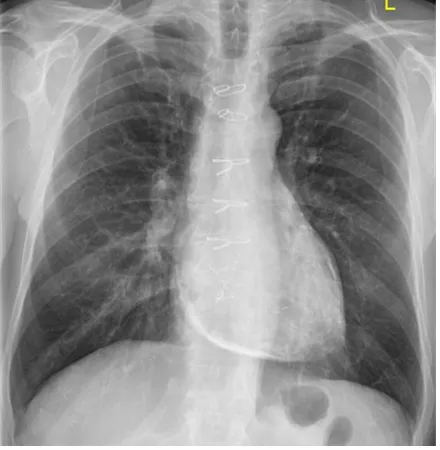

52세 남성이 18개월 전부터 서서히 증가하는 호흡 곤란, 하지 부종 및 지속적인 피로감을 호소하며 내원하였다. 혈압은 110/68 mmHg, 맥박은 분당 78회로 측정되었다. 환자의 흉부 X선 및 CT 영상을 검토한 결과, 다음과 같은 치료 방법을 고려하였다. 가장 적절한 치료 방법은?

흉부 X선과 CT 영상에서 pericardial calcification 소견으로 교착성(또는 압축성)심막염이다. 심낭제거술(pericardiectomy)가 근본적인 치료이다.

이 환자에서 심낭 석회화가 존재한다는 것은 질병이 염증 단계를 넘어 더욱 만성적인 섬유증 또는 석회화 단계로 진행되었음을 의미하며, 수술적 치료(pericardiectomy)가 더 적절하고 결정적인 치료 옵션이 됩니다.